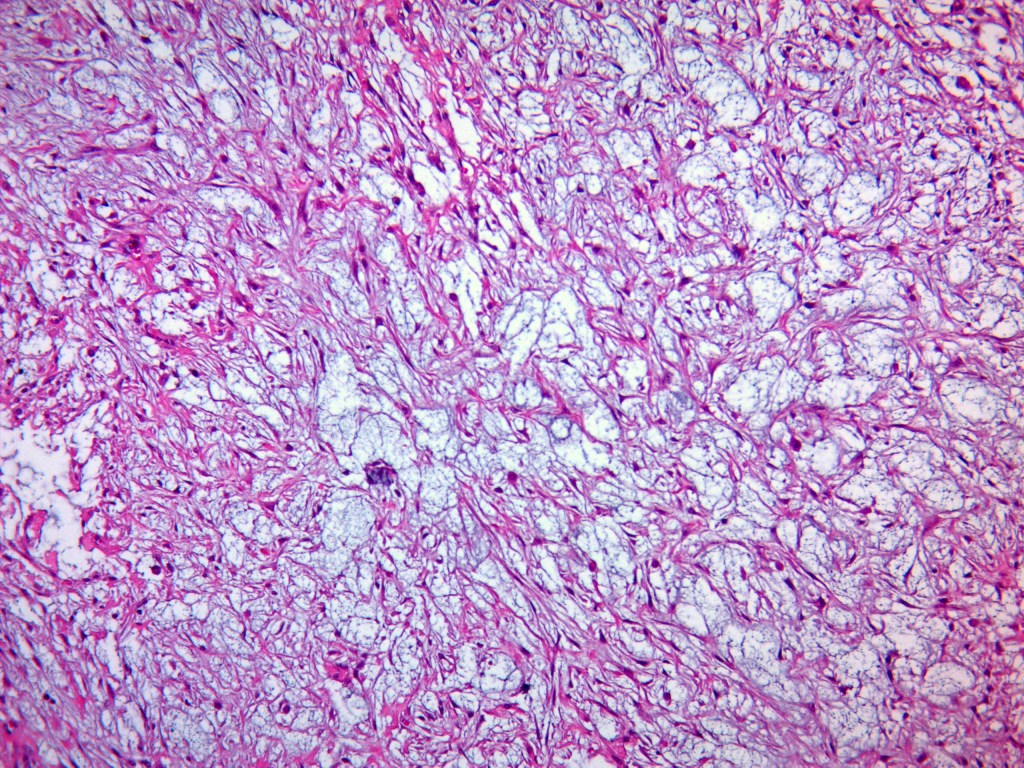

- Well-circumscribed but unencapsulated.

- Borders are well demarcated but may show focal infiltration.

- Composed of plump fibroblasts with eosinophilic cytoplasm, arranged in a short fascicular pattern.

- Abundant loose to myxoid stroma.

- Occasional thick, «keloidal» type collagen.

- Extravasated erythrocytes.

- Histiocytes.

- A few osteoclast-type giant cells—just because.